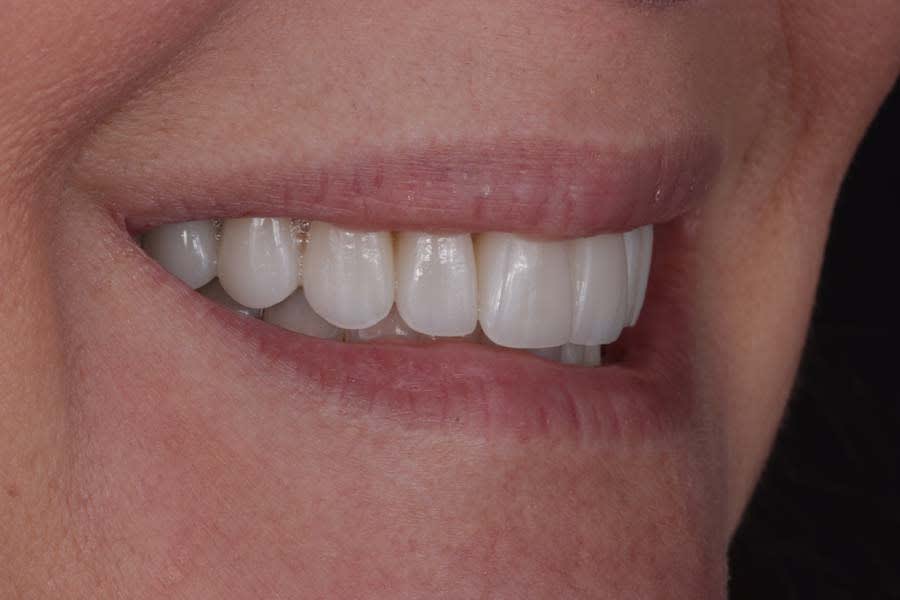

Post-treatment photographs demonstrating the successful outcome of the case are shown in Figure 15 through Figure 19.

Clear aligners (Invisalign) were used to correct gingival margin discrepancies, reduce the black triangle between teeth Nos. 9 and 10, and optimize occlusal forces by uprighting posterior teeth. This orthodontic phase, paired with airway considerations, enabled functional and esthetic improvements without compromising tongue space. Establishing adapted centric posture via deprogramming created a stable occlusal scheme, thereby minimizing risks of further attrition or restoration failure. Lithium-disilicate crowns and resin infiltration restored function and delivered a natural, esthetic smile, with precise laboratory collaboration ensuring accurate shade and contour.

This case exemplifies the transformative potential of a structured, systematic approach in transitioning a patient from single-tooth dentistry to comprehensive care. By addressing biomechanical, functional, periodontal, and dentofacial risks through integrated orthodontic and restorative treatments, the treatment achieved a stable, functional occlusion and an esthetically pleasing smile. The use of clear aligners, precise occlusal management, and cohesive restorations resolved immediate concerns and reduced long-term risks. Since treatment completion in early 2023, the stability of the restorations and the patient’s satisfaction have underscored the success of this approach in delivering lasting functional and esthetic outcomes.